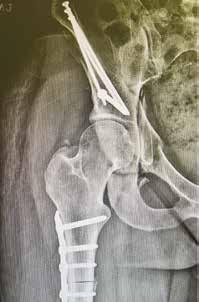

For Rachel, a former basketball, field hockey, soccer, and lacrosse player, that lifestyle has had its challenges. On a deployment to Amman, she experienced severe pain in her left hip. Repeated surgeries stateside did little to resolve the agony for a decade. Then orthopedic surgeon Dr. James Wylie, based at Intermountain Health’s TOSH campus in Murray, ordered a battery of hip-to-toe imaging.

“Dr. Wylie sat me down and said, ‘The bad news is, it’s a textbook case of hip dysplasia—an improper development of the hip joint, causing the socket to be too shallow to fully cover the femoral head—and both of your femurs have significant anteversion; they rotate inward. But the good news is, I can easily fix both at the same time.’ So I was like, ‘Sign me up!’”

In November 2024, Rachel underwent a femoral osteotomy (severing the left femur in two, half-twisting it, and inserting a plate and locking screws) and a periacetabular osteotomy (breaking the hip in three places, then pinning it all back together). Recovery and rehab were lengthy and grueling. But despite the need to relearn to walk, the end of her beloved job, the loss of her dog, and two incidents of home flooding, Rachel never headed off the cliff. She says her marriage, community, and perpetually pragmatic outlook have seen her through the worst.

“I think we did a healthy amount of wallowing,” she acknowledged. “But at some point, you have to get up, feed the dogs, go to the grocery store, and just keep going. Everyone has their peaks and valleys. But we’re healthy, we’re happy, we have a great community here in St. George, and I have a wonderful job. I believe it’s going to be a very good year.”